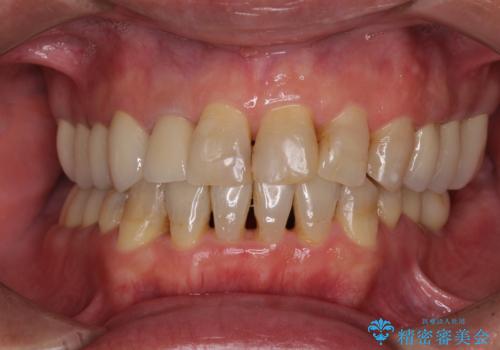

[ 重度歯周病 ] インプラント・義歯による咬合再構築

![[ 重度歯周病 ] インプラント・義歯による咬合再構築の症例 治療後](https://seimitsushinbi.jp/wp/wp-content/uploads/2021/07/4c6838854beaf5801dbc7fde26492d6c-500x350.jpg?v=1626759531)